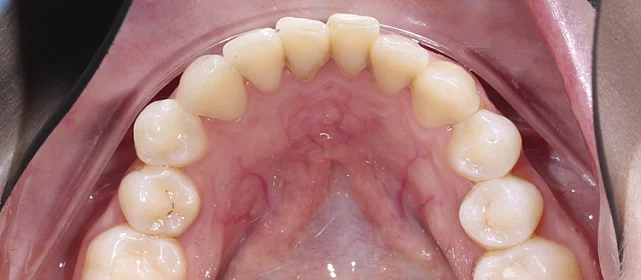

Зубы выровнены, скученность устранена, линия смыкания нормализована. Установлены несъёмные ретейнеры на обе челюсти, сняты слепки для ретенционных кап.

Решение: Поставили элайнеры Click на обе челюсти. Начали с 32 кап, но случай потребовал три дозаказа: 30, 10 и 10 кап — итого 82 капы за 30 месяцев. Количество дозаказов объясняется и сложностью случая (скученность плюс деформация кривой Шпее), и тем, что контрольные визиты были реже обычного из-за проживания за границей. Тем не менее результат достигнут: зубы ровные, смыкание в норме. На ретенцию пациентка приехала отдельно — зафиксировали ретейнеры на обе челюсти, сняли слепки для ретенционных кап.